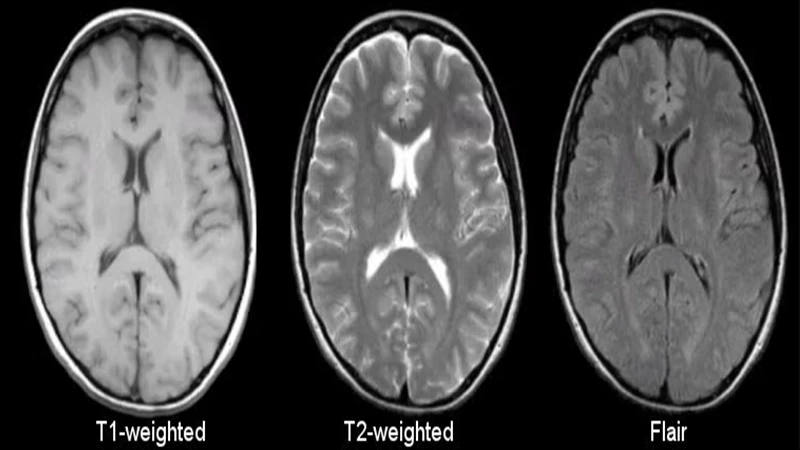

The Language of MRI: T1 and T2 Weighting

The process of protons relaxing back into alignment occurs in two distinct ways, known as T1 and T2 relaxation. By adjusting the timing of the RF pulses and listening for the signal, technologists can create images that emphasize one type of relaxation over the other. This is called "image weighting."

- T1-Weighted Images: In these images, tissues that relax quickly (like fat) appear bright. Tissues that relax slowly (like water and cerebrospinal fluid) appear dark. T1 images are excellent for visualizing normal anatomy and the structure of organs.

- T2-Weighted Images: In these images, tissues that relax slowly (like water and fluid) appear bright. This makes T2 images extremely sensitive for detecting pathology, as many diseases—like tumors, inflammation, and trauma—result in an increase in water content.